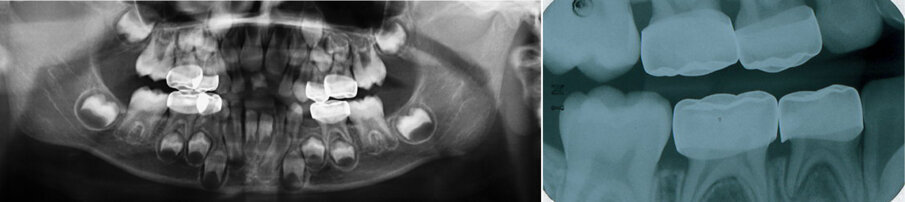

Figure 11 (a & b). The Hall technique: Figure (11a) shows an OPG radiograph taken at follow up for the same patient seen in Figure 10. There were no clinical or radiographic signs or symptoms of pulpal pathosis. Figure (11b) shows a right bitewing radiograph follow up of SSC using the Hall technique. It shows adequate coverage of the primary molars.

All teeth treated with the Hall technique should be followed up clinically and radiographically (see Figure 11) following the same protocols as conventional treatments. The tooth should be assessed for pain, sinuses, swelling and radiographically for signs of interradicular radiolucency or root resorption.